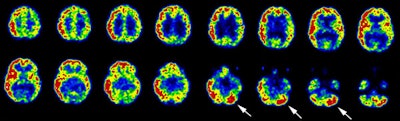

Crossed cerebellar hyperperfusion (diaschisis): The ictal-SPECT exam below demonstrated extensive hyperperfusion (metabolism) involving a large portion of the right cerebral hemisphere. Crossed cerebellar hyperperfusion (white arrows) was also demonstrated on this exam due to neuronal connections between the right brain and left cerebellum. |